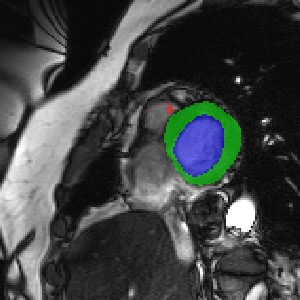

Transformers, the default model of choices in natural language processing, have drawn scant attention from the medical imaging community. Given the ability to exploit long-term dependencies, transformers are promising to help atypical convolutional neural networks (convnets) to overcome its inherent shortcomings of spatial inductive bias. However, most of recently proposed transformer-based segmentation approaches simply treated transformers as assisted modules to help encode global context into convolutional representations without investigating how to optimally combine self-attention (i.e., the core of transformers) with convolution. To address this issue, in this paper, we introduce nnFormer (i.e., Not-aNother transFormer), a powerful segmentation model with an interleaved architecture based on empirical combination of self-attention and convolution. In practice, nnFormer learns volumetric representations from 3D local volumes. Compared to the naive voxel-level self-attention implementation, such volume-based operations help to reduce the computational complexity by approximate 98% and 99.5% on Synapse and ACDC datasets, respectively. In comparison to prior-art network configurations, nnFormer achieves tremendous improvements over previous transformer-based methods on two commonly used datasets Synapse and ACDC. For instance, nnFormer outperforms Swin-UNet by over 7 percents on Synapse. Even when compared to nnUNet, currently the best performing fully-convolutional medical segmentation network, nnFormer still provides slightly better performance on Synapse and ACDC.